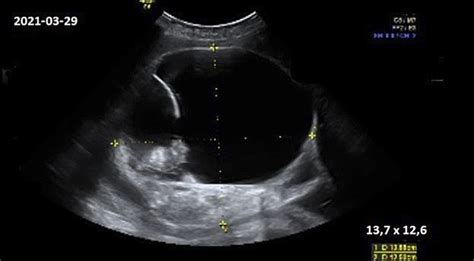

Vaisiaus širdies ritmas nėštumo metu svyruoja nuo 120 iki 160 dūžių per minutę, o vaisius jau nuo 12 savaičių reaguoja į stimulus, įskaitant judesius. Jo smegenų ląstelės intensyviai auga, o judesių įvairovė - pasisukimai, rankų ir kojų judesiai - tampa vis ryškesni. Šie judesiai gali sukelti įvairius garsus, kurie girdimi iš pilvo.